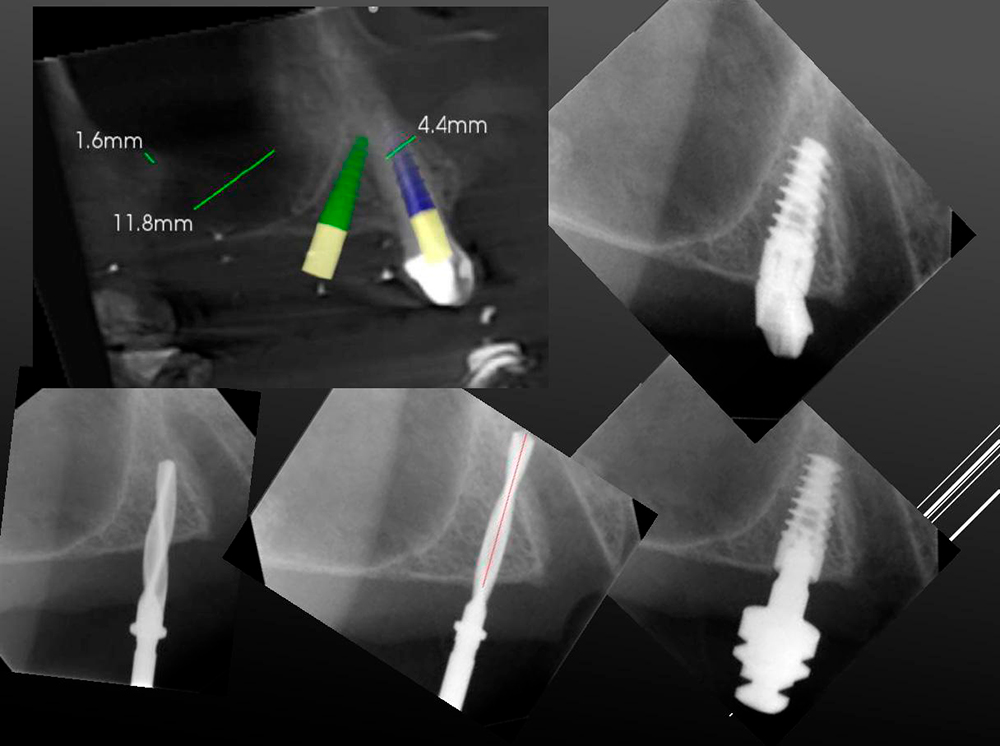

Implant zone 23 Bone available 7.8 x 13.2 Dsi Premium Green Line Implant 3.5x11.5

6.4 x 11.5 m, mm DSI Premium Green Line Implant 3.75 x 10. Density

HU 1332 bone type 1-2